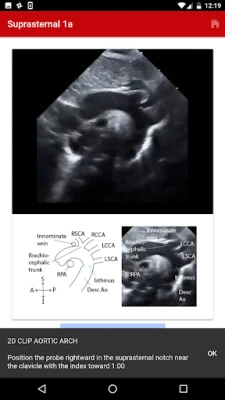

The Echo app provides step-by-step instructions for performing a normal pediatric echocardiogram and uses video clips, images and illustrations to aid in instruction. The app is intended to be used by sonographers at all levels of training, pediatric cardiology fellows, as a teaching aid for pediatric cardiologists and by anyone interested in learning how to perform the normal pediatric echo exam.

There are four standard views where images can be obtained:

1. Subcostal

2. Parasternal

3. Apical

4. Suprasternal

The exact images and the order in which the images and views are obtained varies by institution. Each protocol (subcostal, parasternal, apical or suprasternal) can be followed in order by clicking on the next tab at the bottom of the page or you can click on an individual numbered view within the protocol list to be taken directly to that view. The name of the view and instructions will pop-up automatically at the bottom of the page. The instructions and additional notes can also be found in the “NOTE” button at the bottom of the page.